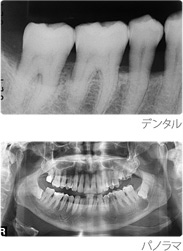

【レントゲン検査(デンタル/パノラマ)】

顎の骨の全体像が分かるパノラマX線写真や、1本1本の歯の詳細が分かるデンタルX線写真を用いた、レントゲン検査を行います。むし歯の存在や、歯周病による骨の溶け具合、骨の中の病変などを詳しく調べます。